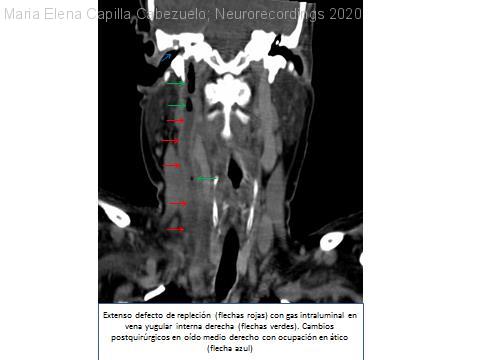

Tromboflebitis séptica de senos venosos y yugular interna y empiema subdural como complicación de otomastoiditis

Diagnóstico final: Tromboflebitis séptica de senos venosos y yugular interna y empiema subdural como complicación de otomastoiditis

Mujer de 60 años intervenida de colesteatoma derecho 5 años antes, con absceso temporal drenado y otitis de repetición posteriores. Ingresa por bacteriemia por Proteus y episodios de disnea y cianosis. En ecografía cervical se observa una trombosis de...